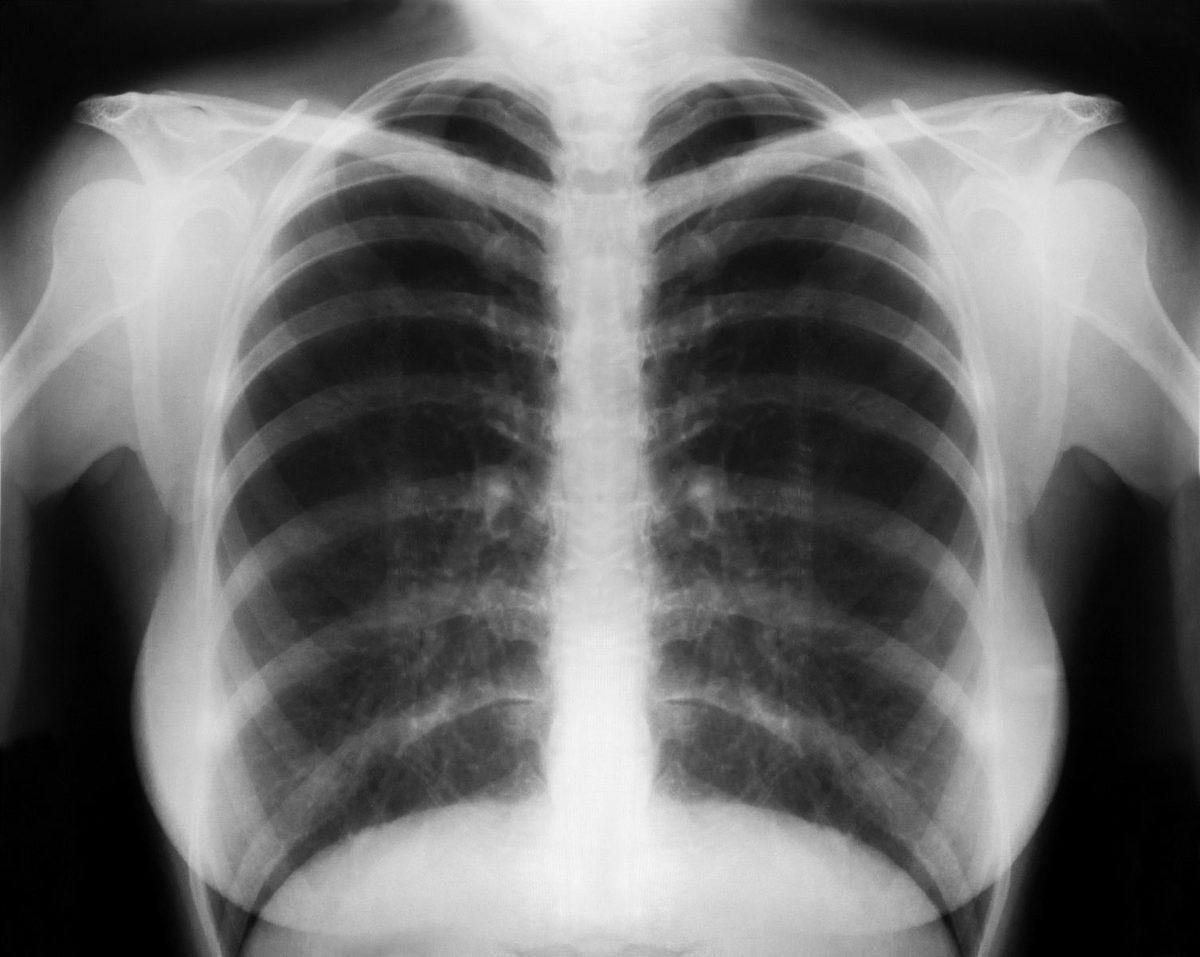

Bugün eğitimsiz olan herhangi bir insana göğüs röntgeni verirseniz size pnömanileri, nodülleri, atelaktazileri gösteremez. Hatta çoğu kişi için bu sözcükler ancak Google’dan aranıp bulunabilecek karışık kavramlardır.

Öte yandan bu ücretsiz internet sitesindeki yapay zeka, yüklenen görselleri yüzde 80 isabet oranıyla yorumluyor. Bir başka ifadeyle ortalama bir radyolog ile aynı başarı yüzdesine sahip.

Chester AI radyoloji asistanı adlı yapay zeka, Montreal Üniversitesi’nden Joseph Paul Cohen tarafından geliştirildi. Yapay zeka görseli tarayarak gerekli sonuçlara ulaşıyor. Her ne kadar Cohen bir tıp doktoru olmasa da sağlık ve derin öğrenme üzerinde çalışıyor. Daha önce BlindTool adlı bir uygulama yazan Cohen, bu uygulamayla görme engelli kişiler için telefon kamerasının kullanılabildiği bir uygulama geliştirmişti.